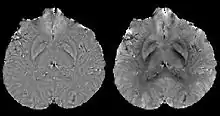

Calculation of susceptibility through multiple orientation sampling (COSMOS)

COSMOS solves the inverse problem by oversampling from multiple orientations.[11][12] COSMOS utilizes the fact that the zero cone surface in the Fourier domain is fixed at the magic angle with respect to the B0 field. Therefore, if an object is rotated with respect to the B0 field, then in the object's frame, the B0 field is rotated and thus the cone. Consequently, data that cannot be calculated due to the cone becomes available at the new orientations.

COSMOS assumes a model-free susceptibility distribution and keeps full fidelity to the measured data. This method has been validated extensively in in vitro, ex vivo and phantom experiments. Quantitative susceptibility maps obtained from in vivo human brain imaging also showed high degree of agreement with previous knowledge about brain anatomy. Three orientations are generally required for COSMOS, limiting the practicality for clinical applications. However, it may serve as a reference standard when available for calibrating other techniques.